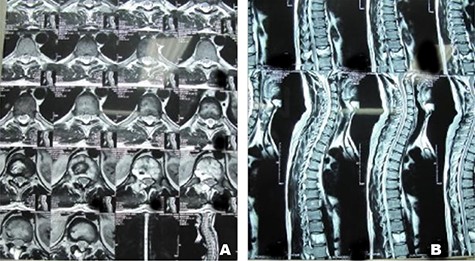

A 24-year-old male presented with acute low back pain with no prior traumatic events. Physical examination was unremarkable except for tenderness over the lower thoracic spine. The laboratory tests including complete blood count, renal function tests, alkaline phosphatase, aspartate aminotransferase, alanine aminotransferase, serum calcium, serum phosphorus and parathyroid hormone were all within normal limits. Initially, the patient was treated conservatively but the pain did not improve. Lumbar X-ray showed mild height loss and fracture of the superior endplate of T12 vertebra (Fig. 1). Computed tomography (CT) showed a multi-lobulated osteolytic lesion within the T12 body with extension to the right pedicle and transverse process (Fig. 2). Magnetic resonance imaging (MRI) revealed a well-defined lesion with low signal intensity on T1 and high signal intensity on T2 weighted images (Fig. 3). The bone scan showed a cold spot at the site of the lesion. The patient underwent surgery and excisional biopsy through the posterior approach. A large clear fluid-filled cavity was curetted and the cavity was filled with an autologous bone graft from iliac crest. Posterior spinal fusion was performed with instrumentation with pedicle screws from T10 to L2 and a mixture of autologous bone graft and allograft was used to achieve better fusion (Fig. 4). Pathology report confirmed the diagnosis of SBC and the patient received no further treatment (Fig. 5). The patient had no recurrence in 10-year follow up.

Case 1, (A): Axial T2-weighted MR image of twelfth thoracic spine vertebrae; (B): Sagittal T2-weightedimages of thoracic spine vertebrae.